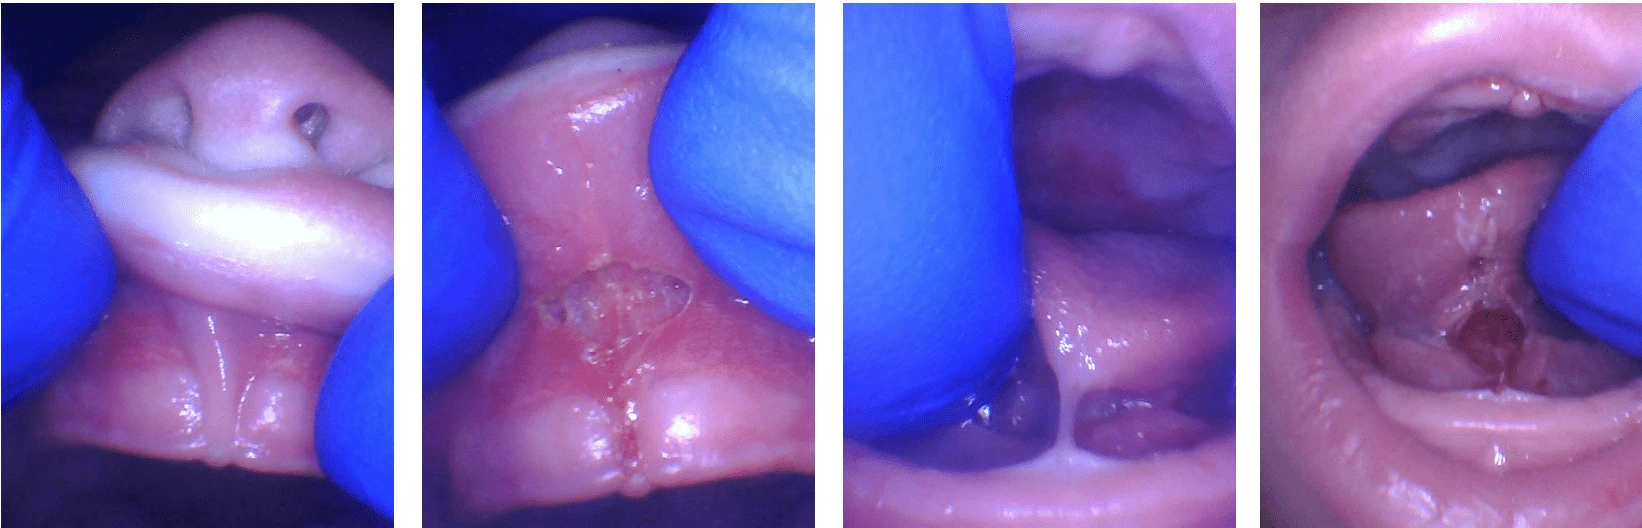

Notice in the photo how the lip will not roll outward when lifted. After the release, it fully lifts to the nose. The tongue is held down all the way to the gum. This is a severe tongue-tie, but even less severe ties can cause similar problems. Afterward, notice how high the tongue can lift with greater mobility.

This is a photo of a posterior tongue-tie. If a baby has symptoms of a tongue-tie (not gaining weight, poor latch, clicking when nursing, gumming the nipple, painful nursing, reflux, gassy, etc.) and there is not an obvious string, it is very likely a posterior tongue-tie. This is a hidden tie that is felt easily but is very often overlooked by medical professionals that have not been trained to identify it.

Notice the picture on the left. It looks like there is no problem, but the baby and mother are having lots of difficulty nursing. When the tongue is lifted with two fingers, notice the tight tissue that pops up. After release, a diamond shape shows that the tongue-tie release was complete and the baby instantly nursed better and mom noticed a huge difference in the depth and quality of the latch. The baby took twice as much milk in half the time they normally spent nursing.